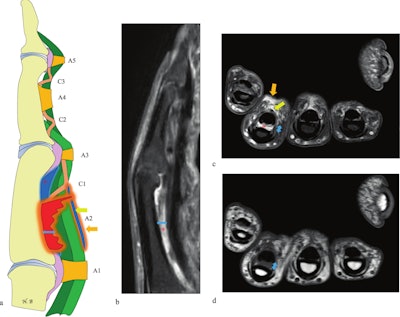

Indirect signs of A2 pulley rupture on MRI.(a) Schematic illustration. (b) Sagittal and (c) axial proton density fat-saturated (PD FS) MRI. (d) Axial T1-weighted MRI. Findings include increased tendon-to-bone distance (double-headed blue arrow), fluid effusion within the tendon sheath (yellow arrow), deep fluid collection surrounding the tendons (asterisk), and perilesional edema superficial to the tendon (orange arrow). On the axial PD FS (c) and T1-weighted (d) images, direct visualization of the A2 pulley rupture is limited, but tendon-to-bone separation is clearly visible on both sagittal and axial views (double-headed blue arrow).Bouredoucen et al; EJR